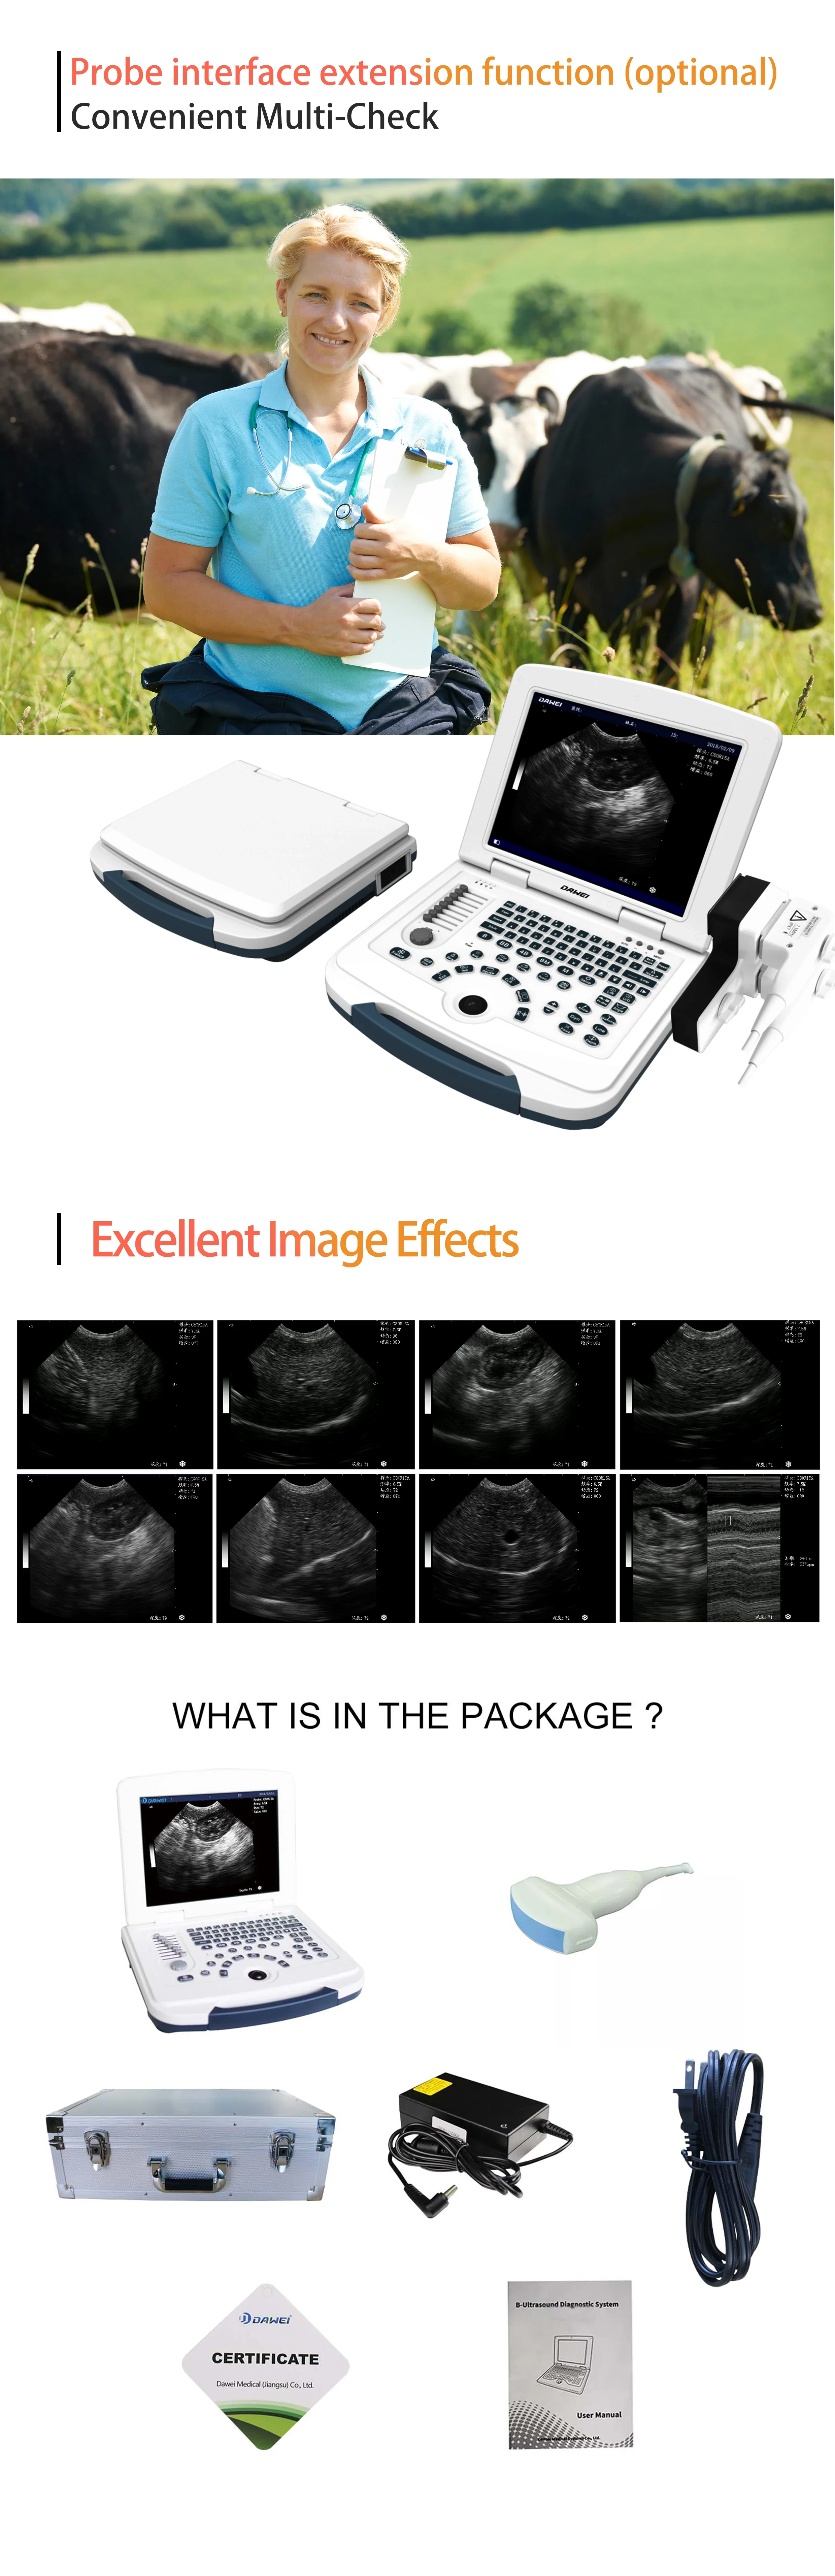

Convex Probe Pictures:

Linear Probe Pictures:

This machine can be used for both humans and animals: